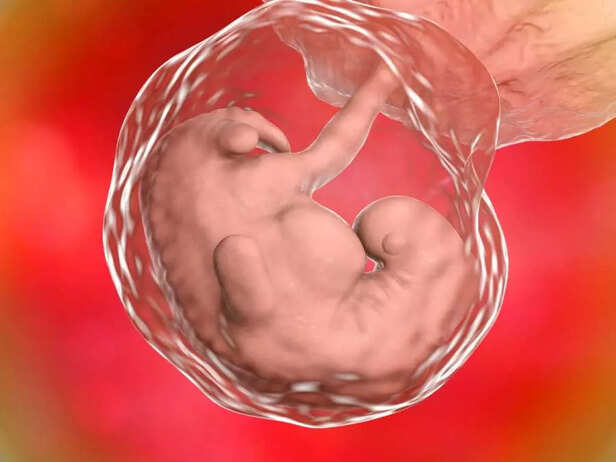

3. Limb Formation Begins

BABY ORGAN FORMATION

In week 6, the foundation for your baby's limbs being is laid down, although they are still in their early stages of development:

a. Upper Limbs:

The upper limbs, which will become the baby's arms, are beginning to grow as small, paddle-like structures coming out from the sides of the body.

b. Lower Limbs:

Similarly, the lower limbs, which will become the baby's legs, are forming as small buds near the area where the hips will be.